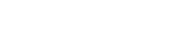

Liver, a key part of human digestive system, is an organ that is responsible for cleaning out toxins from our blood, processing medicines, producing bile, helping you digest fat, storing glucose and producing proteins for clotting your blood, among many other things.